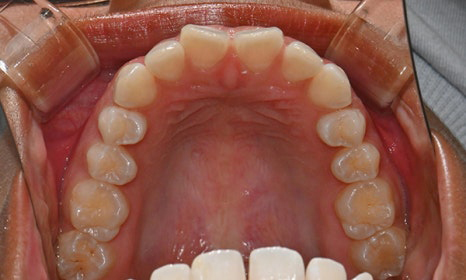

치아 상태는 어땠냐면요:

위아래 앞니 사이에 공간이 벌어져 있었어요.

앞니가 삐뚤빼뚤한 덧니도 있었죠.

윗니와 아랫니가 너무 깊게 맞물리는

과개교합이 있었어요.

왼쪽 아래 작은어금니가 90도 돌아가 있었는데,

이로 인해 왼쪽 치아 배열과 교합이 좋지 않았죠.

초진시 구내사진 (2025. 3.31)